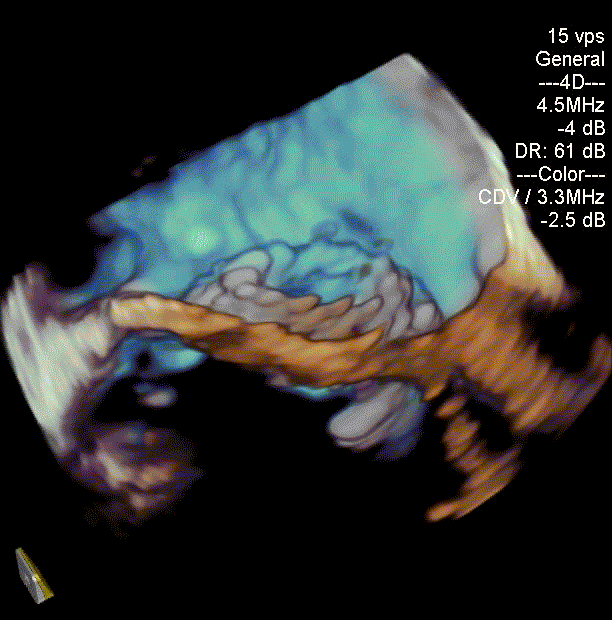

瓣中瓣植入前

二尖瓣重度反流

术后左室造影无反流